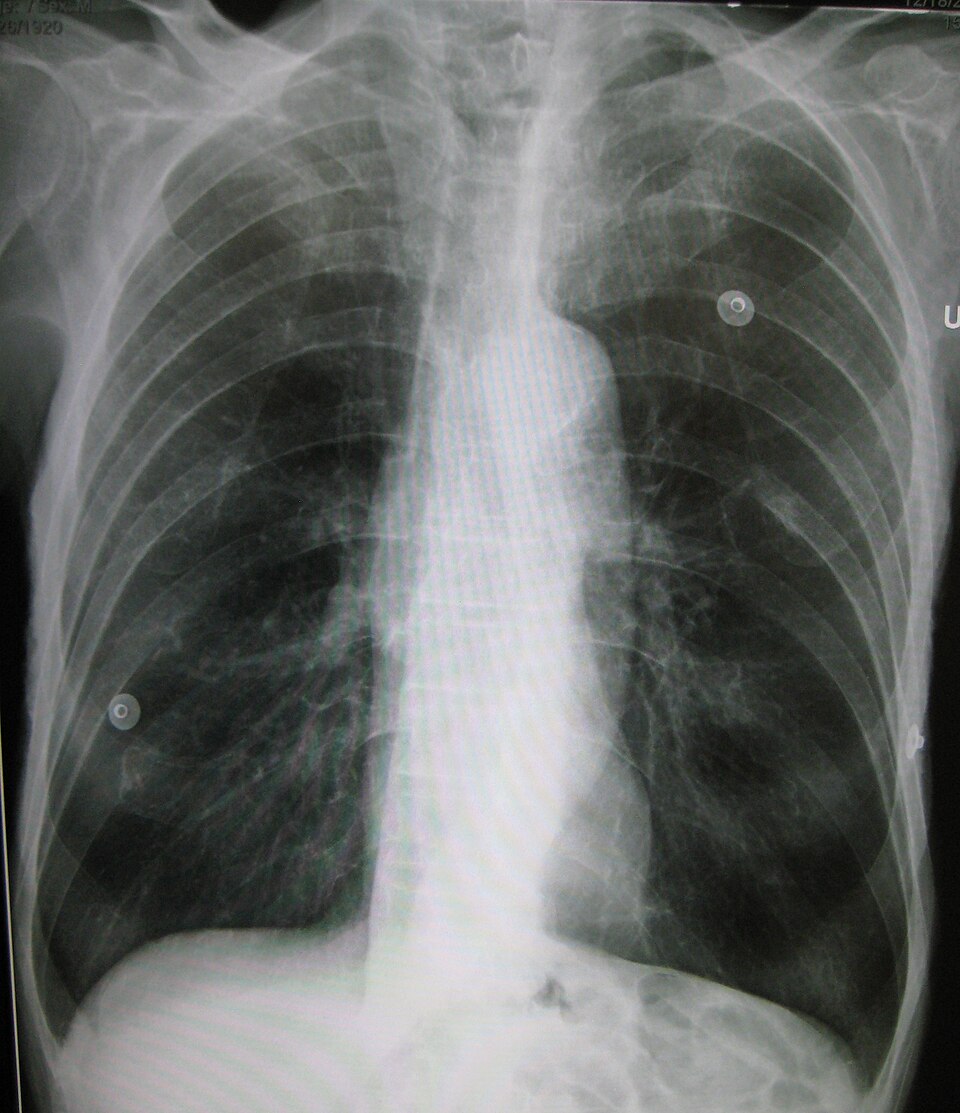

Im Röntgenbild (Röntgen-Thorax) zeigt sich das Lungenemphysem in einer verminderten Dichte des Lungengewebes. Zudem kann ein Tropfenherz ausgebildet sein.